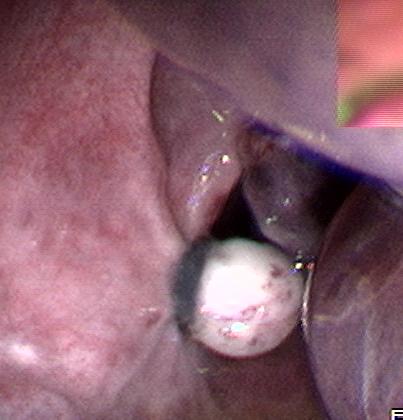

(四)、内镜下胃、肠道息肉切除术

胃、肠道息肉是重要的癌前病变,胃镜、肠镜检查一旦发现有胃、肠道息肉,就应该切除;否则就有癌变的可能。在胃镜或肠镜监视下行息肉电凝切术,是治疗息肉的最佳办法,创伤小,效果好。消化科拥有先进的德国爱尔博(ERBE)高频电凝切仪,配合电子胃镜、肠镜,行息肉电凝切术,效果良好。

肠道息肉切除术后